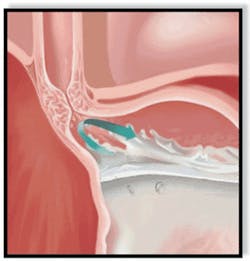

Normally, a ring of muscle tissue called the lower esophageal sphincter, which is located in the lower portion of the esophagus where it joins the stomach (esophagogastric junction), prevents reflux (or backing up) of acid from the stomach (Figures 2--3).

This sphincter relaxes during swallowing to allow food to pass. It then tightens to prevent flow in the opposite direction.

With GERD, however, the sphincter relaxes between swallows, allowing stomach contents and corrosive acid to well up and damage the lining of the esophagus (Figure 4).